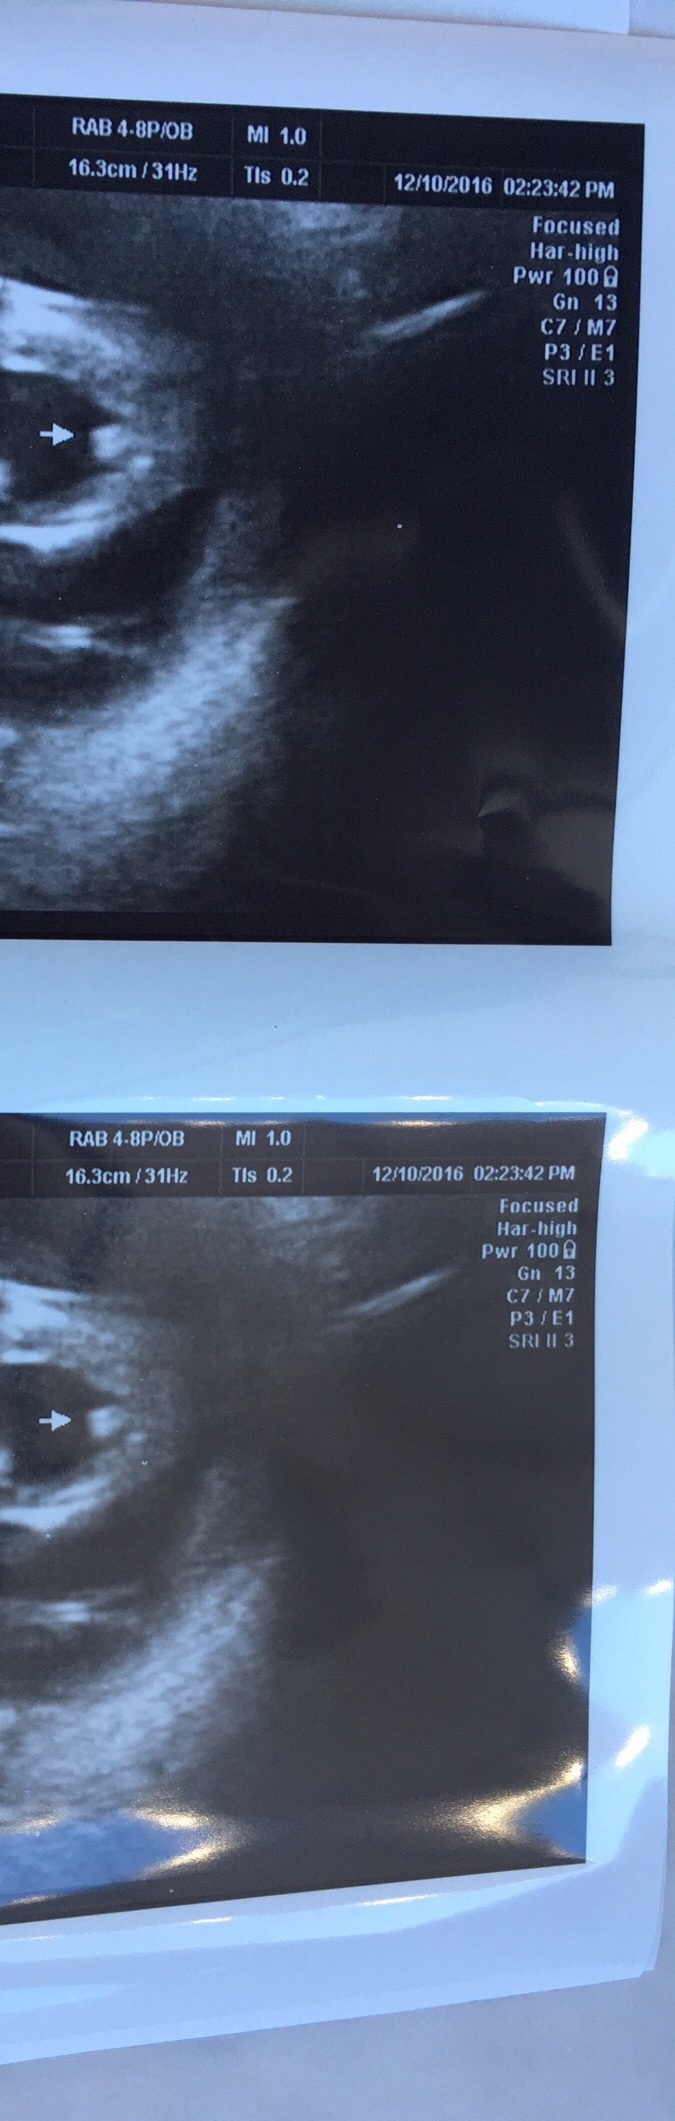

http://uploads.tapatalk-cdn.com/2016...5d046445e3.jpghttp://uploads.tapatalk-cdn.com/2016...5d046445e3.jpg Attachment 34144Attachment 34145